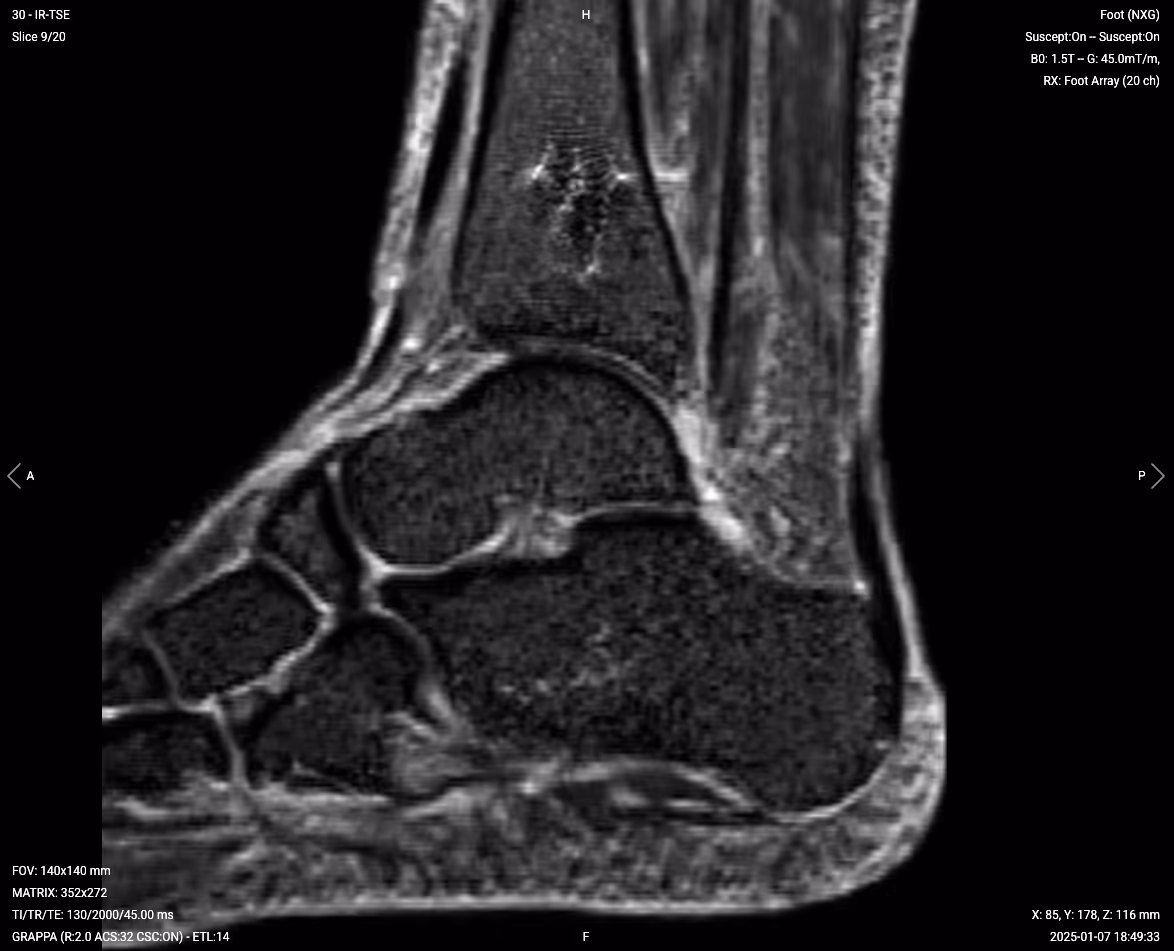

T1 TSE – Highlight Bone and Structural Changes

T1-weighted imaging makes fat appear bright and fluid dark. This contrast is ideal for fat-rich tissues and structural abnormalities. T1 shows anatomical structures clearly, since it helps us see where different solid tissues like muscle and fat meet.

In ankle MRI with metal implants, T1 sequences are key for evaluating the bone-implant interface, detecting loosening, and assessing for avascular necrosis. The bright fat signal helps identify bone marrow changes and stress fractures around the implant.

We capture the sagittal view to assess the ankle from a lateral perspective. This helps evaluate the tibiotalar joint and surrounding structures along the length of the ankle.

Sagittal T1 TSE – Correct Image Example:

Things to Look for in Sagittal T1:

• Clear visualization of bone-implant interface

• Normal bright marrow signal away from metal

• Dark fluid collections suggesting infection

• Structural integrity of surrounding bone